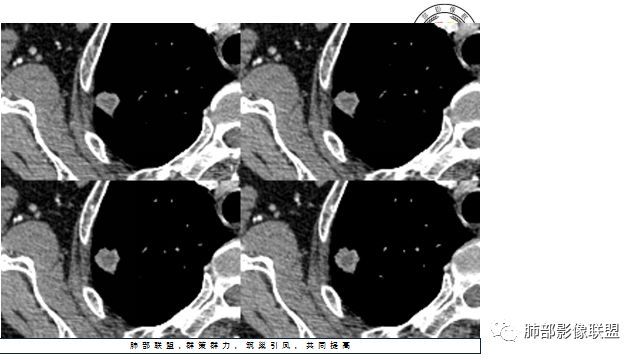

4.增强扫描成明显环形强化,中央液化坏死,内壁清楚且较为规整。

分析:

1.肺鳞癌是容易坏死,但如此小的结节出现影像明显可见的坏死区,且内壁如此清楚规整,我们临床实践中肿瘤非常少见,重要的事情说三遍!!!

病灶缺乏典型的分叶且明显可见的坏死区,腺癌就更为罕见。

2.病灶周边可见薄晕,会想到隐球菌感染,可以出现空洞,但内壁如此清楚的空洞少见。